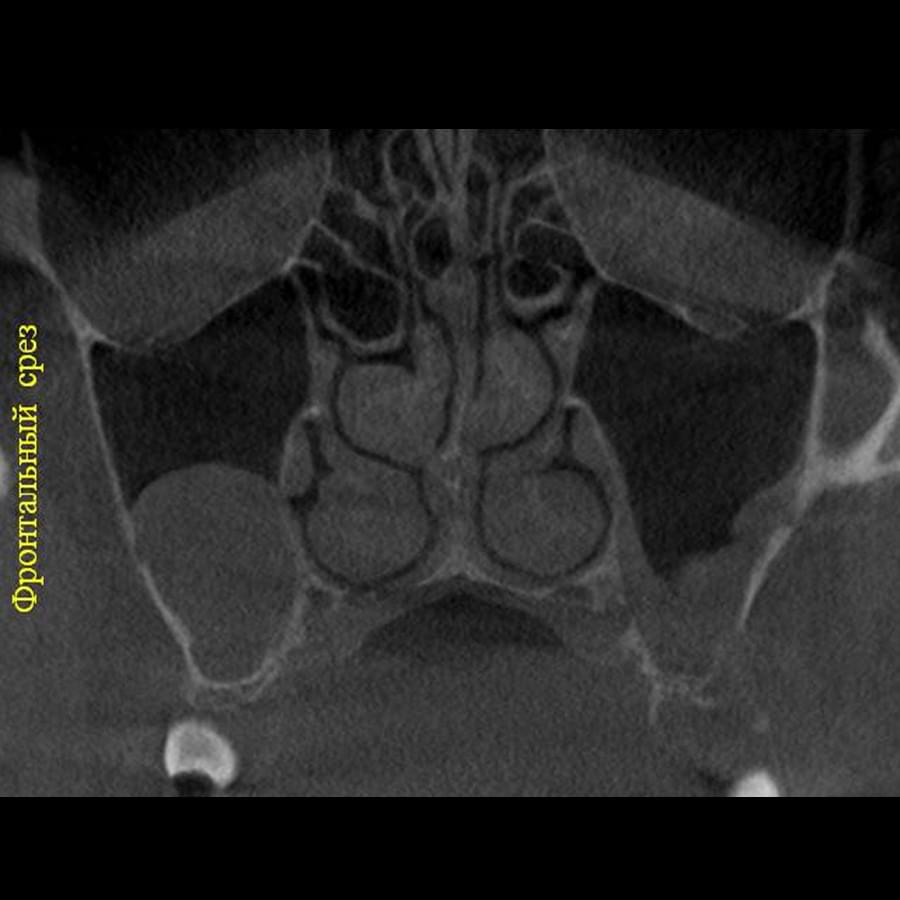

Комп'ютерна томографія

Щелепно-лицева діагностика

Ми використовуємо найсучасніше обладнання відомого виробника PLANMECA, що дозволяє отримувати високоякісні зображення за короткий час. Крім того, ми маємо власний сервер, на якому створюємо окрему скриньку для кожного лікаря, що забезпечує максимальну зручність та ефективність роботи.